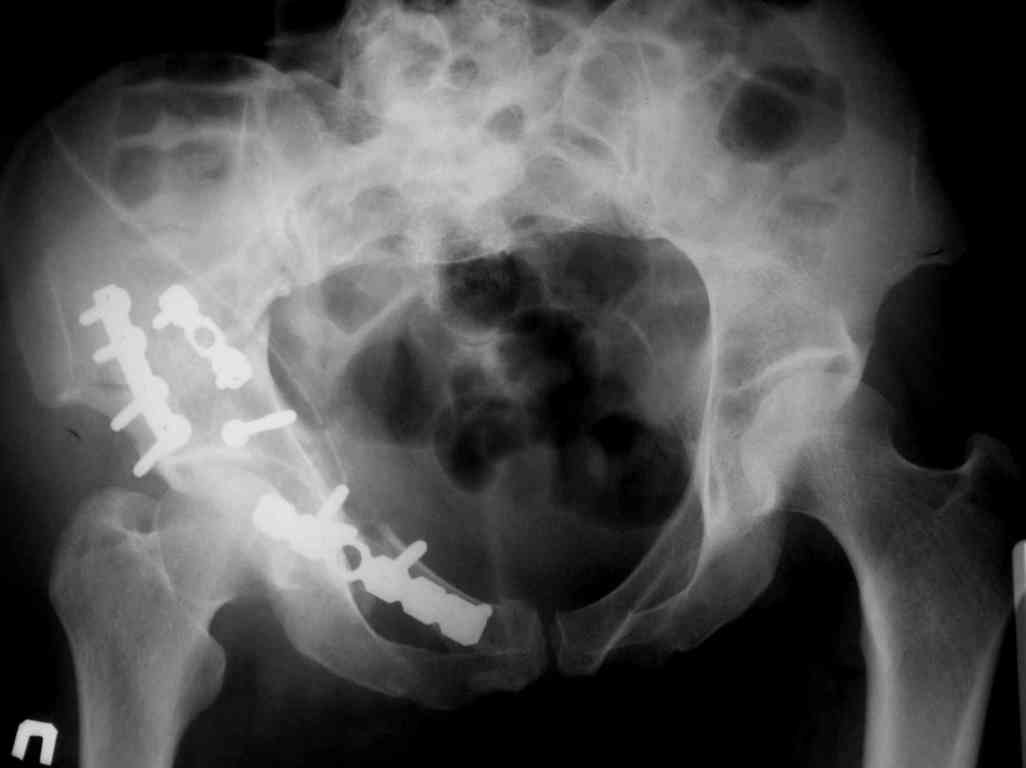

P.S. в приложении R пациентки с похожей проблемой доступа.. за исключением того, что перелом

двухколонный. Вертлугу лечили Y доступом.

К сожалению, далеко не все виды поперечно-ориентированных переломов хорошо лечить задним доступом (неважно на боку или на животе или в среднем положении, что я тоже делал в начале пути). Как только появляются необходимость управления передней колонной (Т-образный перелом, высокий двухколонный, импрессия) возникает выбор - или два доступа или один расширенный, чаще расширенный доступ на боку (Y), удобнее и не так страшно, если перелом оказался вдруг... .

Я предпочитаю в таких случаях расшириться Y-образно, и тогда этих проблем просто нет, тем более, что в этом случае головка извлекается мягко, не царапается хрящ, и репозиция лонноседалищного фрагмента идет сначала через перелом (банальным крючком) и лишь затем из седалищной вырезки (так спокойнее за седалищный нерв).